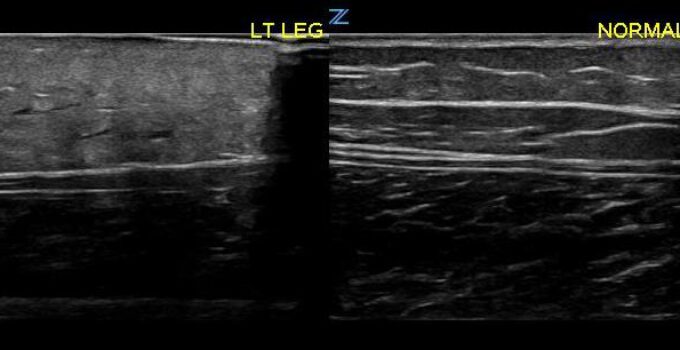

Yüzeyel Ultrasonda Normal Bulgular

Yatak başı ultrasonografi için tipik olarak kullanılan ekipmanla epidermis ve dermis ayırt edilemez. Birlikte ince, hiperekoik bir katman olarak görünürler.

Subkutan tabaka ultrasonda hipoekoik görünür, iki bileşen vardır: hiperekoik yağ ile serpiştirilmiş hipoekoik lineer ekolar çoğunlukla cilde paralel, bağ dokusu septasını temsil eder.

Deri altı tabakasında damarlar ve sinirler görüntülenebilir.

Fasya lineer hiperekoik bir tabaka olarak görünür. Kalınlığı bulunduğu yere göre değişir.

Kas fasikülleri, onları çevreleyen hiperekoik bağ dokusu (perimisyum) ile hipoekoik silindirik yapılar olarak görselleştirilebilir.

Kasın karakteristik bir özelliği, ultrasondaki görünümünün kasılma ile değişmesidir; büzüldüğünde, kısa eksenli düzlemlerde daha kalın ve daha yankılı görünür.